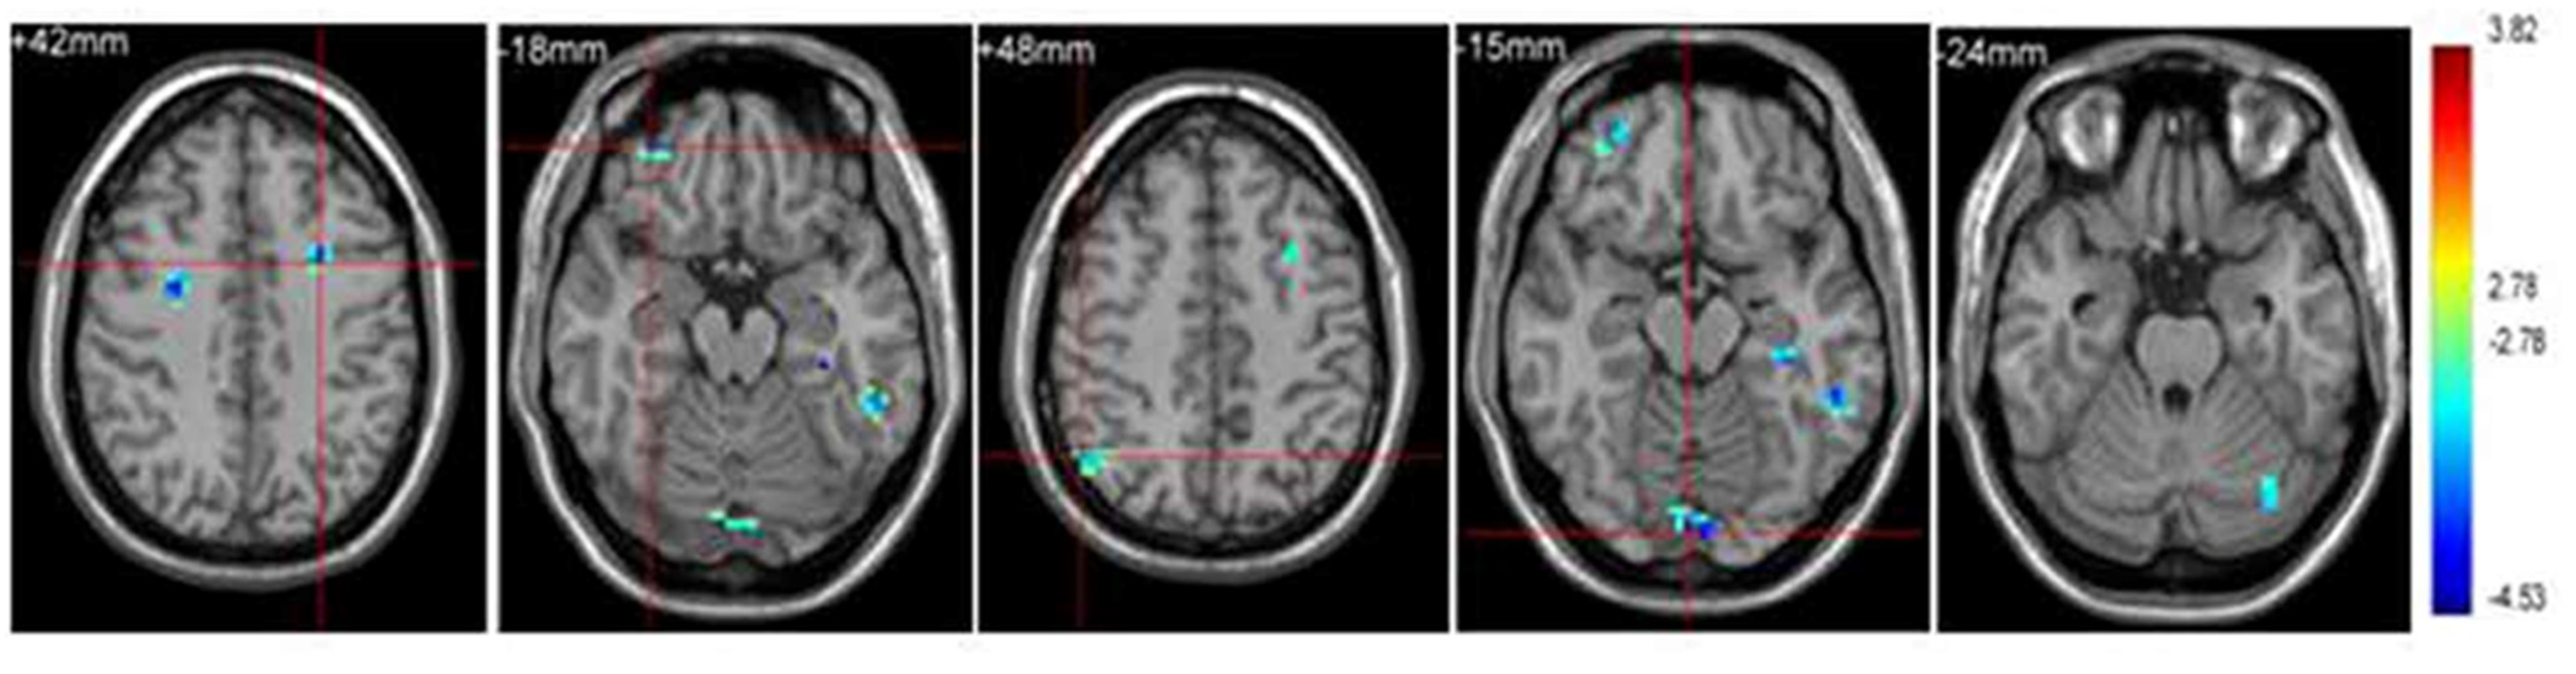

- Yu, Q.; Herold, F.; Becker, B.; Klugah-Brown, B.; Zhang, Y.; Perrey, S.; Veronese, N.; Müller, N.G.; Kramer, A.F.; Zou, L. Cognitive benefits of exercise interventions: An fMRI activation likelihood estimation meta-analysis. Brain Struct. Funct. 2021, 226, 601–619. [Google Scholar] [CrossRef]

| Brain Region | Side | x | y | z | Voxels | t-Value |

|---|---|---|---|---|---|---|

| Precuneus (BA 31) | R | 11 | −74 | 23 | 52 | 8.52 |

| Anterior insula (BA 13) | L | −42 | −6 | −0 | 136 | 7.88 |

| Anterior cingulate cortex (BA 32) | R | 2 | 32 | 6 | 35 | 6.32 |

| Inferior frontal gyrus (BA 9) | L | −45 | 11 | 33 | 48 | 6.75 |

| Inferior parietal lobule (BA 3) | L | −45 | −24 | 44 | 75 | 7.50 |